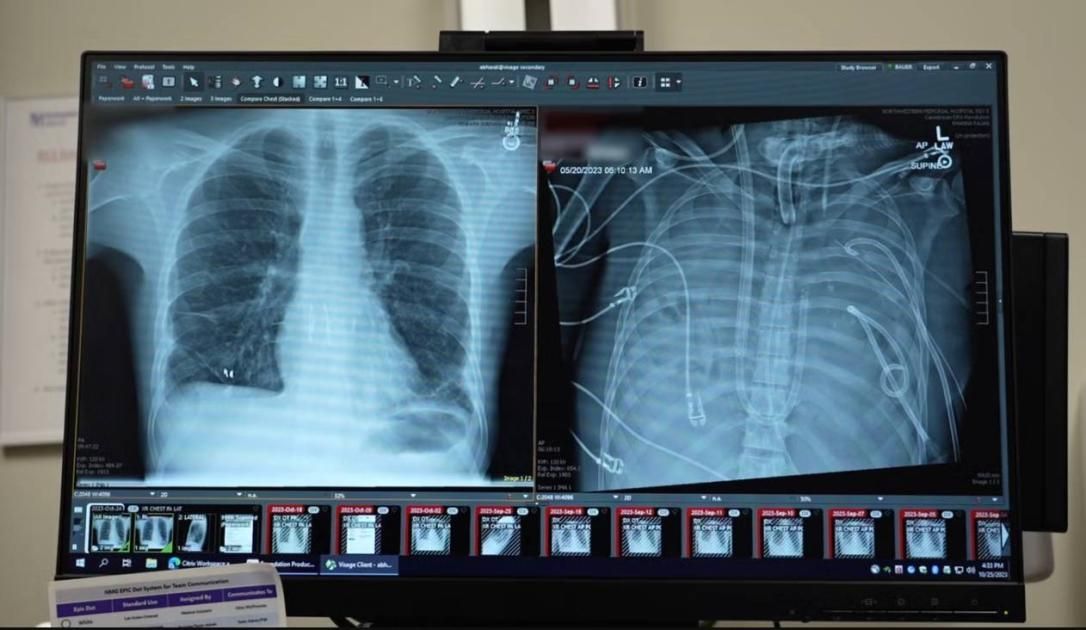

أصيب الرجل بمتلازمة الضائقة التنفسية الحادة نتيجة التهاب إنفلونزا، ما تسبب في تدهور رئتيه بسرعة وإصابته بالتهاب رئوي بكتيري حاد، أدى في نهاية المطاف إلى فشل قلبه وكليتيه ورئتيه، وأصبح زرع الرئتين الخيار الوحيد لإنقاذ حياته.

وأضاف: كان جسم المريض أضعف من أن يقبل رئتين جديدتين ويحتاج إلى مزيد من الوقت للشفاء من الالتهاب، لذلك صممنا له رئة اصطناعية مؤقتة تقوم بوظائف الأكسجة وإزالة ثاني أكسيد الكربون، والحفاظ على استقرار تدفق الدم عبر الجسم حتى تتوفر رئتا المتبرع.

وتابع: بعد يومين، أصبحت رئتا المتبرع متاحتين وأجريت للمريض عملية زرع رئة مزدوجة بنجاح وعاد إلى حياته اليومية بوظائف رئوية طبيعية.